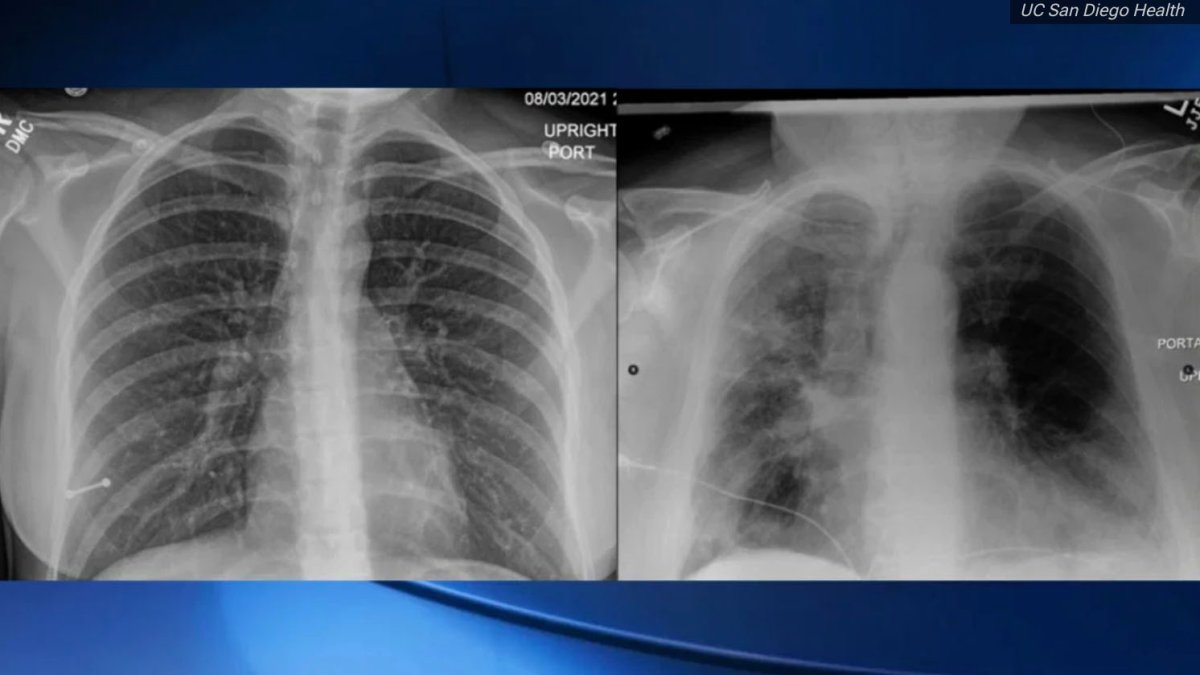

Un doctor que evaluó radiografías de pulmones de pacientes con el virus, vacunados y no vacunados contra el COVID-19 dijo que las imágenes muestran el impacto que la inmunización tiene en la prevención de enfermedades severas.

El doctor Tim Morris, un especialista en pulmones y en terapia intensiva de la Universidad de San Diego, dijo que no es necesaria una capacitación técnica para ver la diferencia: en la izquierda están los pulmones de una persona vacunada contra el COVD-19 y en la derecha, la del paciente no vacunado, según reporta NBC Bay Area.

LA DIFERENCIA ENTRE LAS RADIOGRAFÍAS ES CONTRASTANTE

La radiografía de la izquierda muestra muchas más zonas oscuras lo cual es normal y significa que los pulmones están llenos de aire, según el doctor Morris.

Mientras que la radiografía del paciente no vacunado muestra más zonas grises, más nubladas, lo que quiere decir que los pulmones presentan infecciones.

‘’Esa es una señal de neumonía del COVID-19’’, dijo sobre el paciente no vacunado mientras que la radiografía del paciente vacunado muestra a la vacuna en funciones.